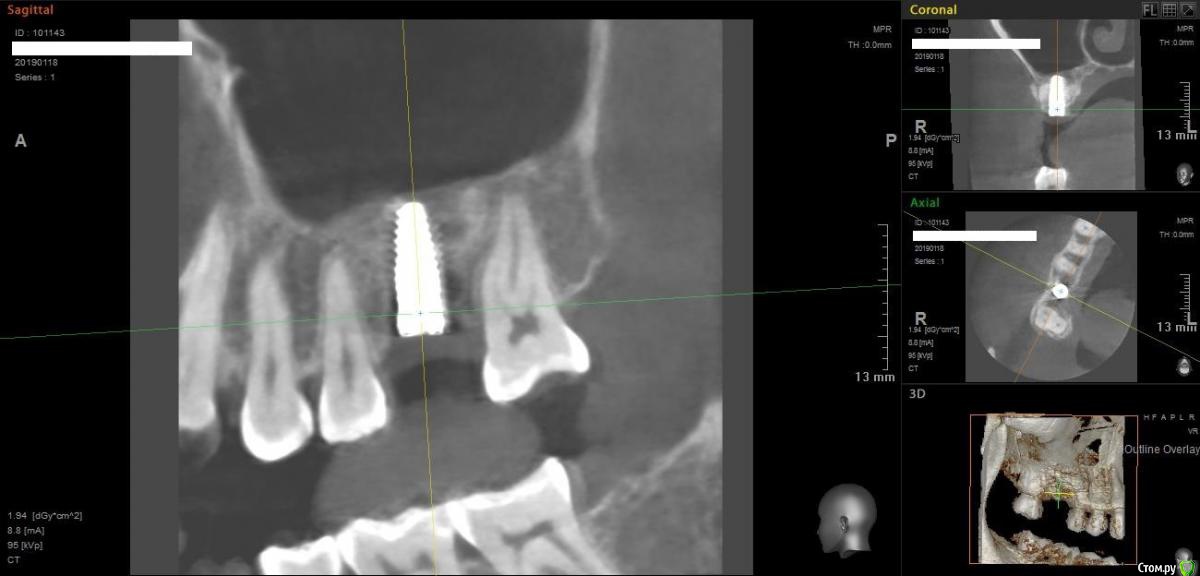

Norton Опубликовано 14 апреля, 2019 Поделиться Опубликовано 14 апреля, 2019 (изменено) Доброго времени суток уважаемые коллеги. Ко мне обратилась пациентка с установленным импл. в области верхней 6 (XIVE 3.8 / 11 мм). Сейчас назревает вопрос нужна ли мягкотканная пластика или нет? Cмутило то, что несколько коллег в моем городе порекомендовали сделать. Изменено 14 апреля, 2019 пользователем Norton Ссылка на комментарий

Дмитрий М Опубликовано 18 апреля, 2019 Поделиться Опубликовано 18 апреля, 2019 (изменено) отлом вестибулярной или миграция графта?похоже свободный фрагмент, пальпируется нет? Изменено 18 апреля, 2019 пользователем Дмитрий М Ссылка на комментарий

Magadalina Опубликовано 19 апреля, 2019 Поделиться Опубликовано 19 апреля, 2019 Похоже на выход графта сразу после синус- лифтинга через окно. Это никакого значения не имеет Ссылка на комментарий

Norton Опубликовано 20 апреля, 2019 Автор Поделиться Опубликовано 20 апреля, 2019 что это.jpg отлом вестибулярной или миграция графта?похоже свободный фрагмент, пальпируется нет?Нет, я на это тоже обратил внимание Ссылка на комментарий